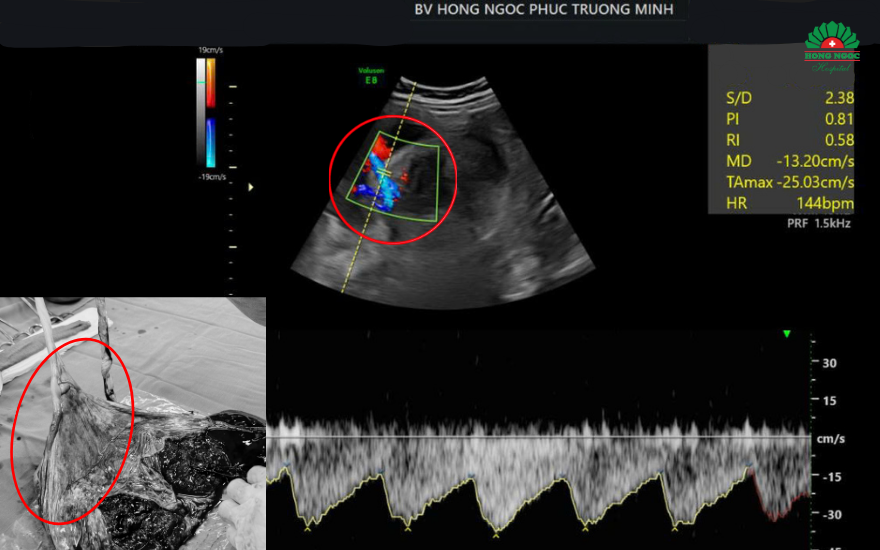

Hình ảnh dây rốn bám màng trên siêu âm và thực tế.

Siêu âm 4D và Doppler màu chuyên sâu: Với hệ thống máy siêu âm hiện đại Voluson Expert 22 cùng kỹ thuật STIC DOPPLER, bác sĩ có thể đánh giá rõ hình thái thai nhi, vị trí bám của dây rốn, dòng chảy động mạch rốn, lượng máu đến bánh nhau... Từ đó phát hiện sớm bất thường như dây rốn bám màng, rau cài răng lược, thiếu ối,…